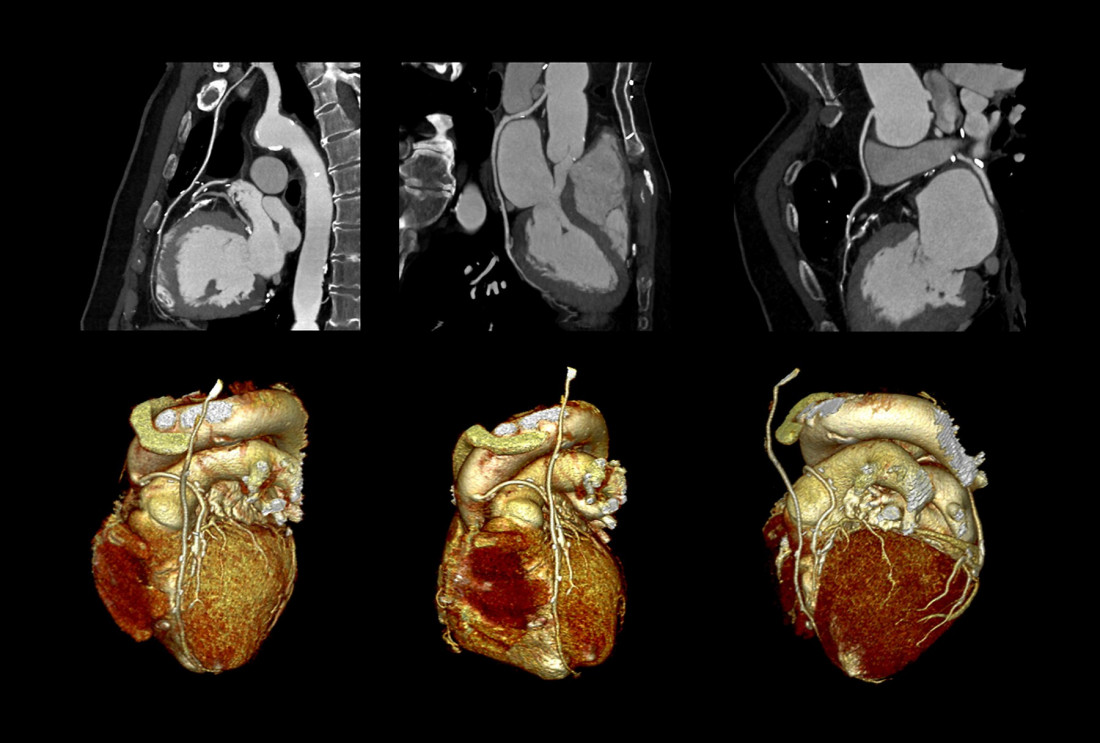

ZEPHYR / Sciencephoto / Profimedia